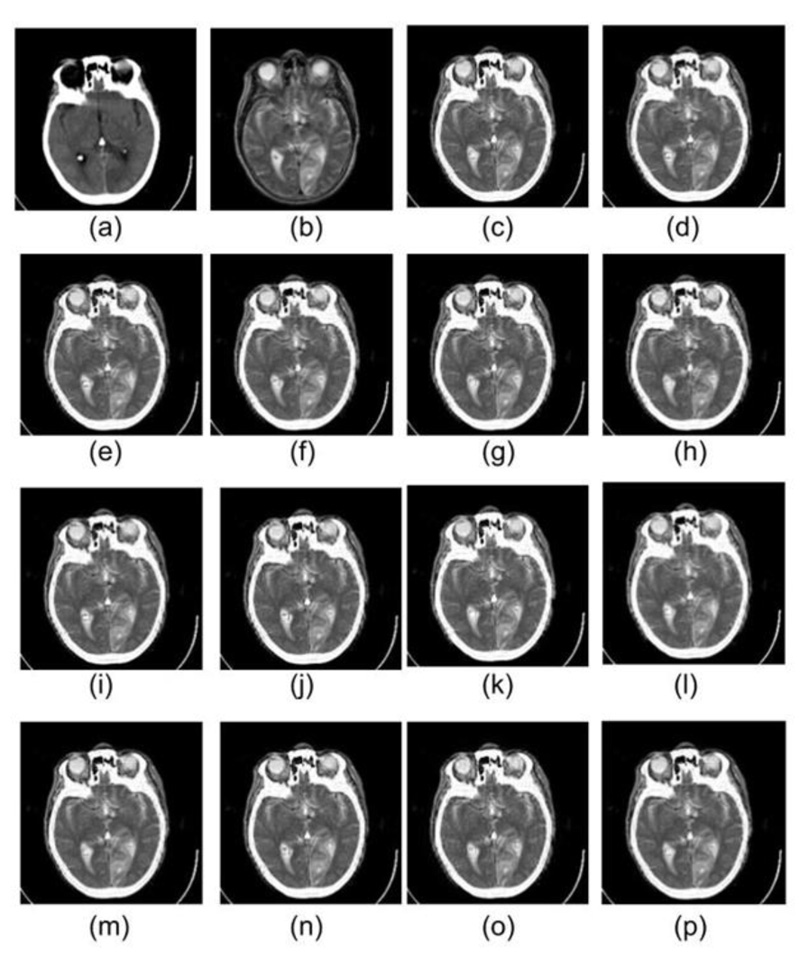

All the 120 wavelet filters are exhaustively tested on all three datasets. Out of 120 wavelet family members, those who have produced better-fused images in terms of visualization are as follows: Haar, db1 & db2 (Daubechies wavelet family), sym2 & sym4 (Symlets wavelet family), coif2 & Coif4 (Coiflet wavelet family), fk4 & fk6 (Fejer-Korovkin wavelet family), dmey (DMeyer wavelet family), bior2.2 & bior2.4 (Biorthogonal wavelet family), and rbio 1.1 & rbio1.3 (Reverse Biorthogonal wavelet family). The top two results of all the eight families in terms of both visual appearance as well as quantitative parameters are displayed here.

Figs. (2-6) represent the input dataset used and the corresponding fused images obtained using the following wavelets: db1, db2, sym2, sym4, coif2, coif4, fk4, fk6, bior 2.2, bior 2.4, rbio 1.1, rbio1.3, dmey, and Haar. In Fig. (3), the input CT and MRI images from dataset 1, which are fused using different wavelet family members, are displayed in 4(a) and 4(b), respectively. Since soft tissues of the brain are best scanned with MRI, whereas bone information is collected with CT, therefore the best fusion method should preserve information of the soft tissues from MRI, whereas information of the bones must be taken from CT image. Analyzing the fused images represented in Fig. (4), it has been observed that the texture of the soft tissues present in MRI got mixed with the information of the soft tissue in CT, due to which texture loss in the soft tissues is visible in all the fused images obtained with different wavelets. However, comparing all the fused images with each other, it can be seen that the texture of the soft tissues is somewhat better visible in the fused images obtained from db1, rbio 1.1, and Haar wavelets.

Dataset 1 consists of MRI and CT scans having metastatic bronchogenic carcinoma, which is visible in the MRI scan compared to the CT scan. It should appear the same in the fused images as it appears in the MRI. It has been observed that metastatic bronchogenic carcinoma is visible in all the fused images, as illustrated in Fig. (4). However, since the soft tissue texture is visible in a better way from the fused images obtained using db1, rbio 1.1, and Haar wavelets, therefore the contrast between the soft tissue and the carcinoma is better in the three fused images as compared to fused images obtained from other wavelets.

As it comes to the bone structure information present in the fused images, it has been observed that some information loss took place in the fused images. Although bone appears good in CT, the transition from the skull to the brain is smoother as compared to the MRI scans. Thus the boundary of the skull is pretty visible in the MRI. Consequently, when the fusion rule is applied, it emphasizes the edges of MRI, and it is evident in the results of all the wavelet family members.

Similarly, in Figs. (5 and 6), images (a) and (b) represent CT & MRI input images of datasets 2 and 3, respectively. The remaining images in both the figures are the fused images obtained by the application of selected wavelets families. For these two datasets also db1, rbio1.1, and Haar wavelet have produced better visual quality fused images, which are in line with dataset 1 discussed earlier in detail.